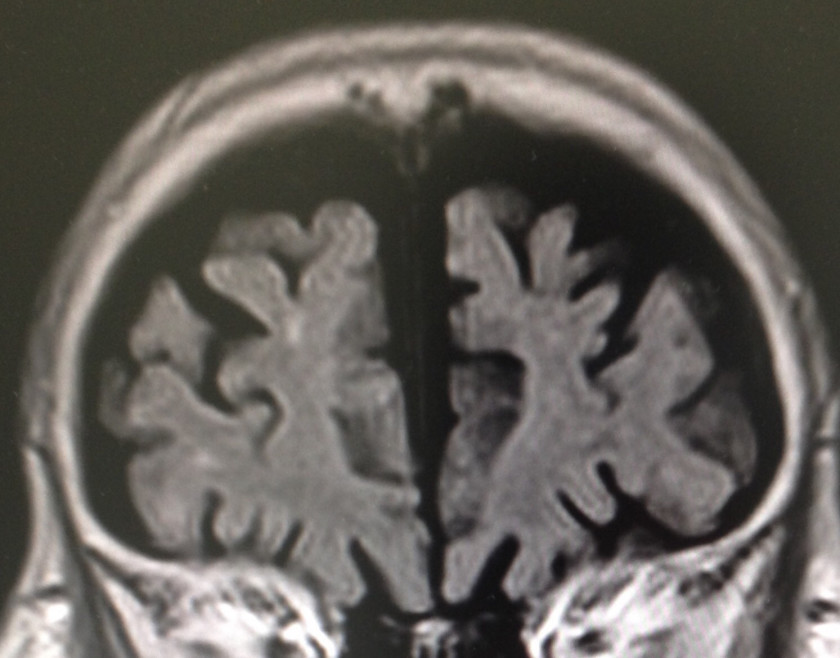

90代前半の症例。風貌は“長身の老紳士”。記憶の問題あり。

虚血性心疾患の既往もあり。認知機能テストは低得点。MRIも裏付ける内容。他スライスでも明らかな、広汎な白質病変を伴う左右差のある強烈な海馬萎縮。AGDを疑わせるような行動異常は認めず。アルツハイマーにおける海馬萎縮の左右差頻度は拙著に記載した通り、珍しくもなし。年齢的にNFTDとの鑑別は当然だが、過剰リン酸化タウオンリーよりも、アミロイドβ+過剰リン酸化タウのコラボがこの強烈な海馬萎縮の元凶と“妄想”。処方されていたメマリーでノイズを消すことよりも、既往歴と白質病変から考えるに優先すべきことがあるのでは❓

ポリファマシーを避けるべく、処方しても“1種類”。他にも問題を見つけたので、そちらを改善してから・・・。